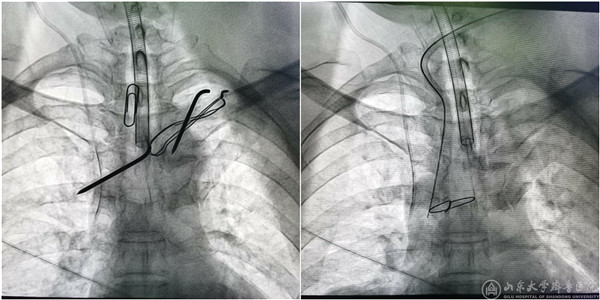

(钢针取出前后钢针透视)

8月26日下午,在第一手术室的杂交手术间,杨长勇教授作为主刀医生、桑锡光教授作为助手,经多学科联合协作,成功将嵌于患者纵膈内的钢针取出。术中见钢针横卧在无名静脉前面,被血管被膜增生组织包绕,几次分离都面临大出血的风险,最终顺利取出钢针。目前,患者术后恢复良好并顺利出院。